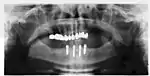

Success or failure of implants depends primarily on the thickness and health of the bone and gingival tissues that surround the implant, but also on the health of the person receiving the treatment and drugs which affect the chances of osseointegration. The amount of stress that will be put on the implant and fixture during normal function is also evaluated. Planning the position and number of implants is key to the long-term health of the prosthetic since biomechanical forces created during chewing can be significant. The position of implants is determined by the position and angle of adjacent teeth, by lab simulations or by using computed tomography with CAD/CAM simulations and surgical guides called stents. The prerequisites for long-term success of osseointegrated dental implants are healthy bone and gingiva. Since both can atrophy after tooth extraction, pre-prosthetic procedures such as sinus lifts or gingival grafts are sometimes required to recreate ideal bone and gingiva.

When a more exacting plan is needed beyond clinical judgment, the dentist will make an acrylic guide (called a stent) prior to surgery which guides optimal positioning of the implant. Increasingly, dentists opt to get a CT scan of the jaws and any existing dentures, then plan the surgery on CAD/CAM software. The stent can then be made using stereolithography following computerized planning of a case from the CT scan. The use of CT scanning in complex cases also helps the surgeon identify and avoid vital structures such as the inferior alveolar nerve and the sinus.[31][32]: 1199

An implant is tested between 8 and 24 weeks to determine if it is integrated. There is significant variation in the criteria used to determine implant success, the most commonly cited criteria at the implant level are the absence of pain, mobility, infection, gingival bleeding, radiographic lucency or peri-implant bone loss greater than 1.5 mm.[65]

Dental implant success is related to operator skill, quality and quantity of the bone available at the site, and the patient's oral hygiene, but the most important factor is primary implant stability.[66] While there is significant variation in the rate that implants fail to integrate (due to individual risk factors), the approximate values are 1 to 6 percent[28]: 68 [51]

Long-term failures are due to either loss of bone around the tooth and/or gingiva due to peri-implantitis or a mechanical failure of the implant. Because there is no dental enamel on an implant, it does not fail due to cavities like natural teeth. While large-scale, long-term studies are scarce, several systematic reviews estimate the long-term (five to ten years) survival of dental implants at 93–98 percent depending on their clinical use.[1][2][3] During initial development of implant retained teeth, all crowns were attached to the teeth with screws, but more recent advancements have allowed placement of crowns on the abutments with dental cement (akin to placing a crown on a tooth). This has created the potential for cement, that escapes from under the crown during cementation to get caught in the gingiva and create a peri-implantitis (see picture below). While the complication can occur, there does not appear to be any additional peri-implantitis in cement-retained crowns compared to screw-retained crowns overall.[68] In compound implants (two stage implants), between the actual implant and the superstructure (abutment) are gaps and cavities into which bacteria can penetrate from the oral cavity. Later these bacteria will return into the adjacent tissue and can cause periimplantitis.

Criteria for the success of the implant supported dental prosthetic varies from study to study, but can be broadly classified into failures due to the implant, soft tissues or prosthetic components or a lack of satisfaction on the part of the patient. The most commonly cited criteria for success are function of at least five years in the absence of pain, mobility, radiographic lucency and peri-implant bone loss of greater than 1.5 mm on the implant, the lack of suppuration or bleeding in the soft tissues and occurrence of technical complications/prosthetic maintenance, adequate function, and esthetics in the prosthetic. In addition, the patient should ideally be free of pain, paraesthesia, able to chew and taste and be pleased with the esthetics.[65]